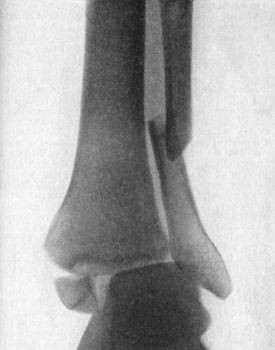

90 38.Radiogram of Incomplete Backward Dislocation of Elbow

91 39.Forward Dislocation of Elbow, with Fracture of Olecranon